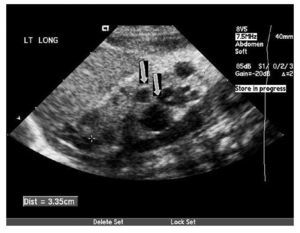

Fig. 1. Riñón izquierdo: se objetivan múltiples quistes no comunicantes en el polo inferior (flechas), reconociéndose tejido renal en el tercio medio.